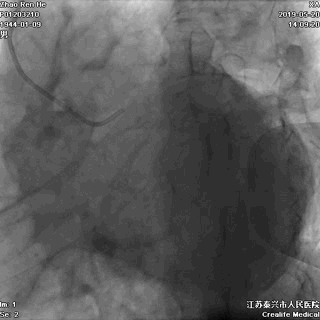

二、双侧冠状动脉造影(1周后)

LCX提供侧枝逆向供应右冠

侧枝血管粗,弯曲小而少